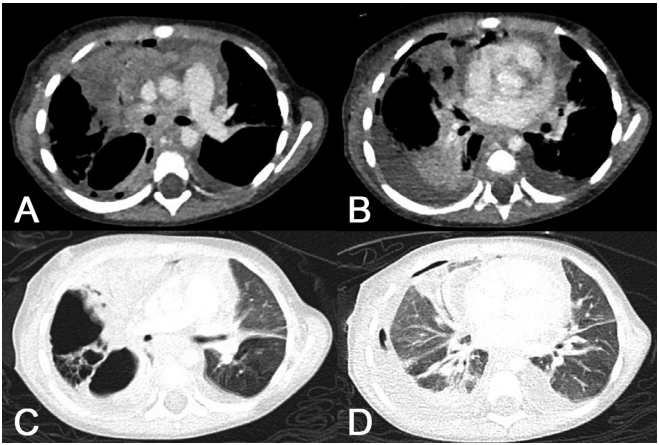

患者的胸水穿刺和水封引流 (WSD) 显示出混浊的黄色、浆液脓性胸水。细胞学检查显示胸膜液由间皮细胞、巨噬细胞和淋巴细胞组成。未发现恶性肿瘤细胞。胸部CT扫描显示右肺1-5段不均匀实变,多个空洞,右上支气管分支狭窄,提示NP,主肺动脉窗及隆突下淋巴结病变,右肺积水,左胸腔积液(图3)。

图3. 住院第1天进行的CT扫描显示右肺不均匀实变